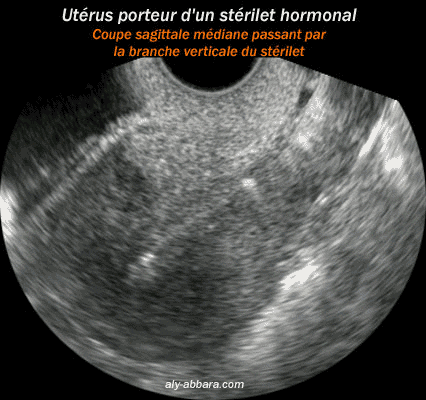

ou DIU (dispositif intra-utérin) hormonal

L'emplacement dans l'utérus vu par l'échographie

La tige (branche verticale) du stérilet (coupe sagittale médiane sur l'utérus)

A comparer à l'aspect échographique du stérilet non hormonal (, )